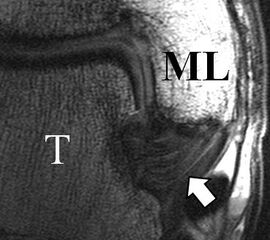

Zu Fehlinterpretationen eines intakten LFTA führt unter Umständen das unmittelbar kaudal des LFTA parallel verlaufende Ligamentum talocalcaneum laterale (Abb. 9 a). Dieses kann bei Verwendung von Schichtdicken um die 3 mm trotz Ruptur des LFTA durch Volumenteileffekte mit Anschnittsphänomenen einen intakten Bandverlauf vortäuschen.

Eine Ursache der falschen Diagnose einer LFTA-Ruptur ist die Fehlinterpretation der physiologische Bandlücke zwischen dem LFTA und der vorderen Syndesmose als traumatischer Banddefekt (Abb. 9 b).

Die Interpretation pathologischer Veränderungen sollte daher immer multiplanar unter Verwendung möglichst dünner Schichtdicken und hoher Ortsauflösungen erfolgen, um Fehldiagnosen zu vermeiden.